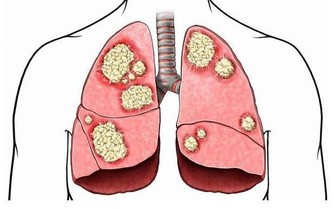

血管是我們身體的運輸渠道,如果血管裡出現了“髒東西”的話,這些“髒東西”會隨著血液的流動遍布人的全身,“髒東西”多了還會堵住血管,危害極大。

可能你會說,“臟東西”多了清理乾淨就好了唄,當然沒那麼簡單。想要清理這些“臟東西”,首先你要了解它們是什麼,然後才好對症下藥。

血管中的“臟東西”指的是甘油三酯、膽固醇,隨著人年齡的增大,這些“臟東西”會在血管壁上慢慢累積,導致血液流動受阻,這就是老年人更容易得腦血栓、心腦血管病、高血壓等疾病的原因。